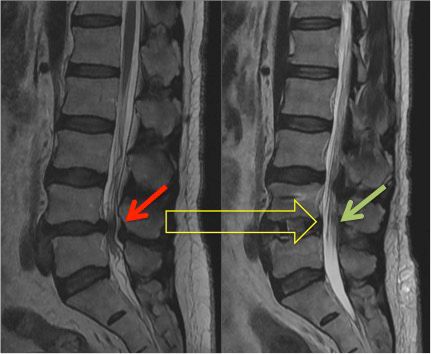

Slipped Disc: Causes, Symptoms, Treatment & Full Recovery Guide

Slip Disc: Causes, Symptoms, Diagnosis, Treatment & Management By Dr. Saijyot Raut, Consultant Spine Surgeon at One Spine 08/11/2025 | 7 Min read Facebook Youtube Instagram What is a Slip Disc? We receive many calls/inquiries at our clinic where patients are constantly talking about feeling numbness and tingling in the leg and lower back pain. […]